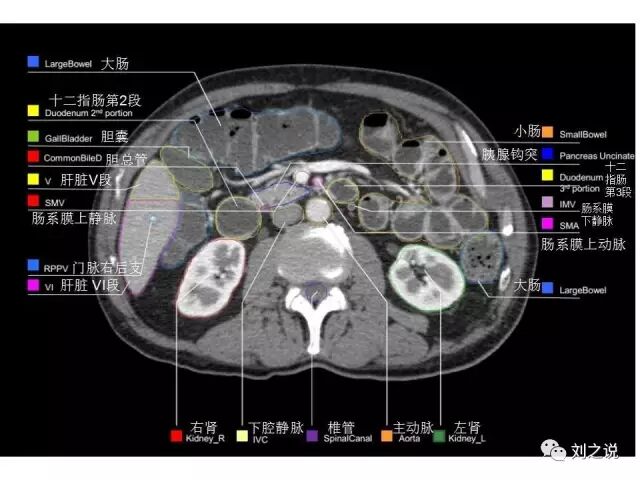

参考RTOG共识和3D-body解剖。

来源:刘之说